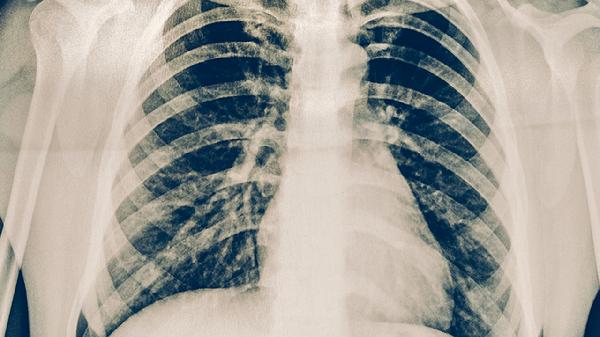

肺脓肿是肺组织坏死形成的脓腔,与肺结核空洞均可出现咳嗽、咯脓痰、发热。肺脓肿起病急骤,痰液恶臭且量多;肺结核空洞发展缓慢,痰中带血更常见。肺脓肿CT显示液平面,治疗需长程抗生素如克林霉素磷酸酯注射液,必要时引流。